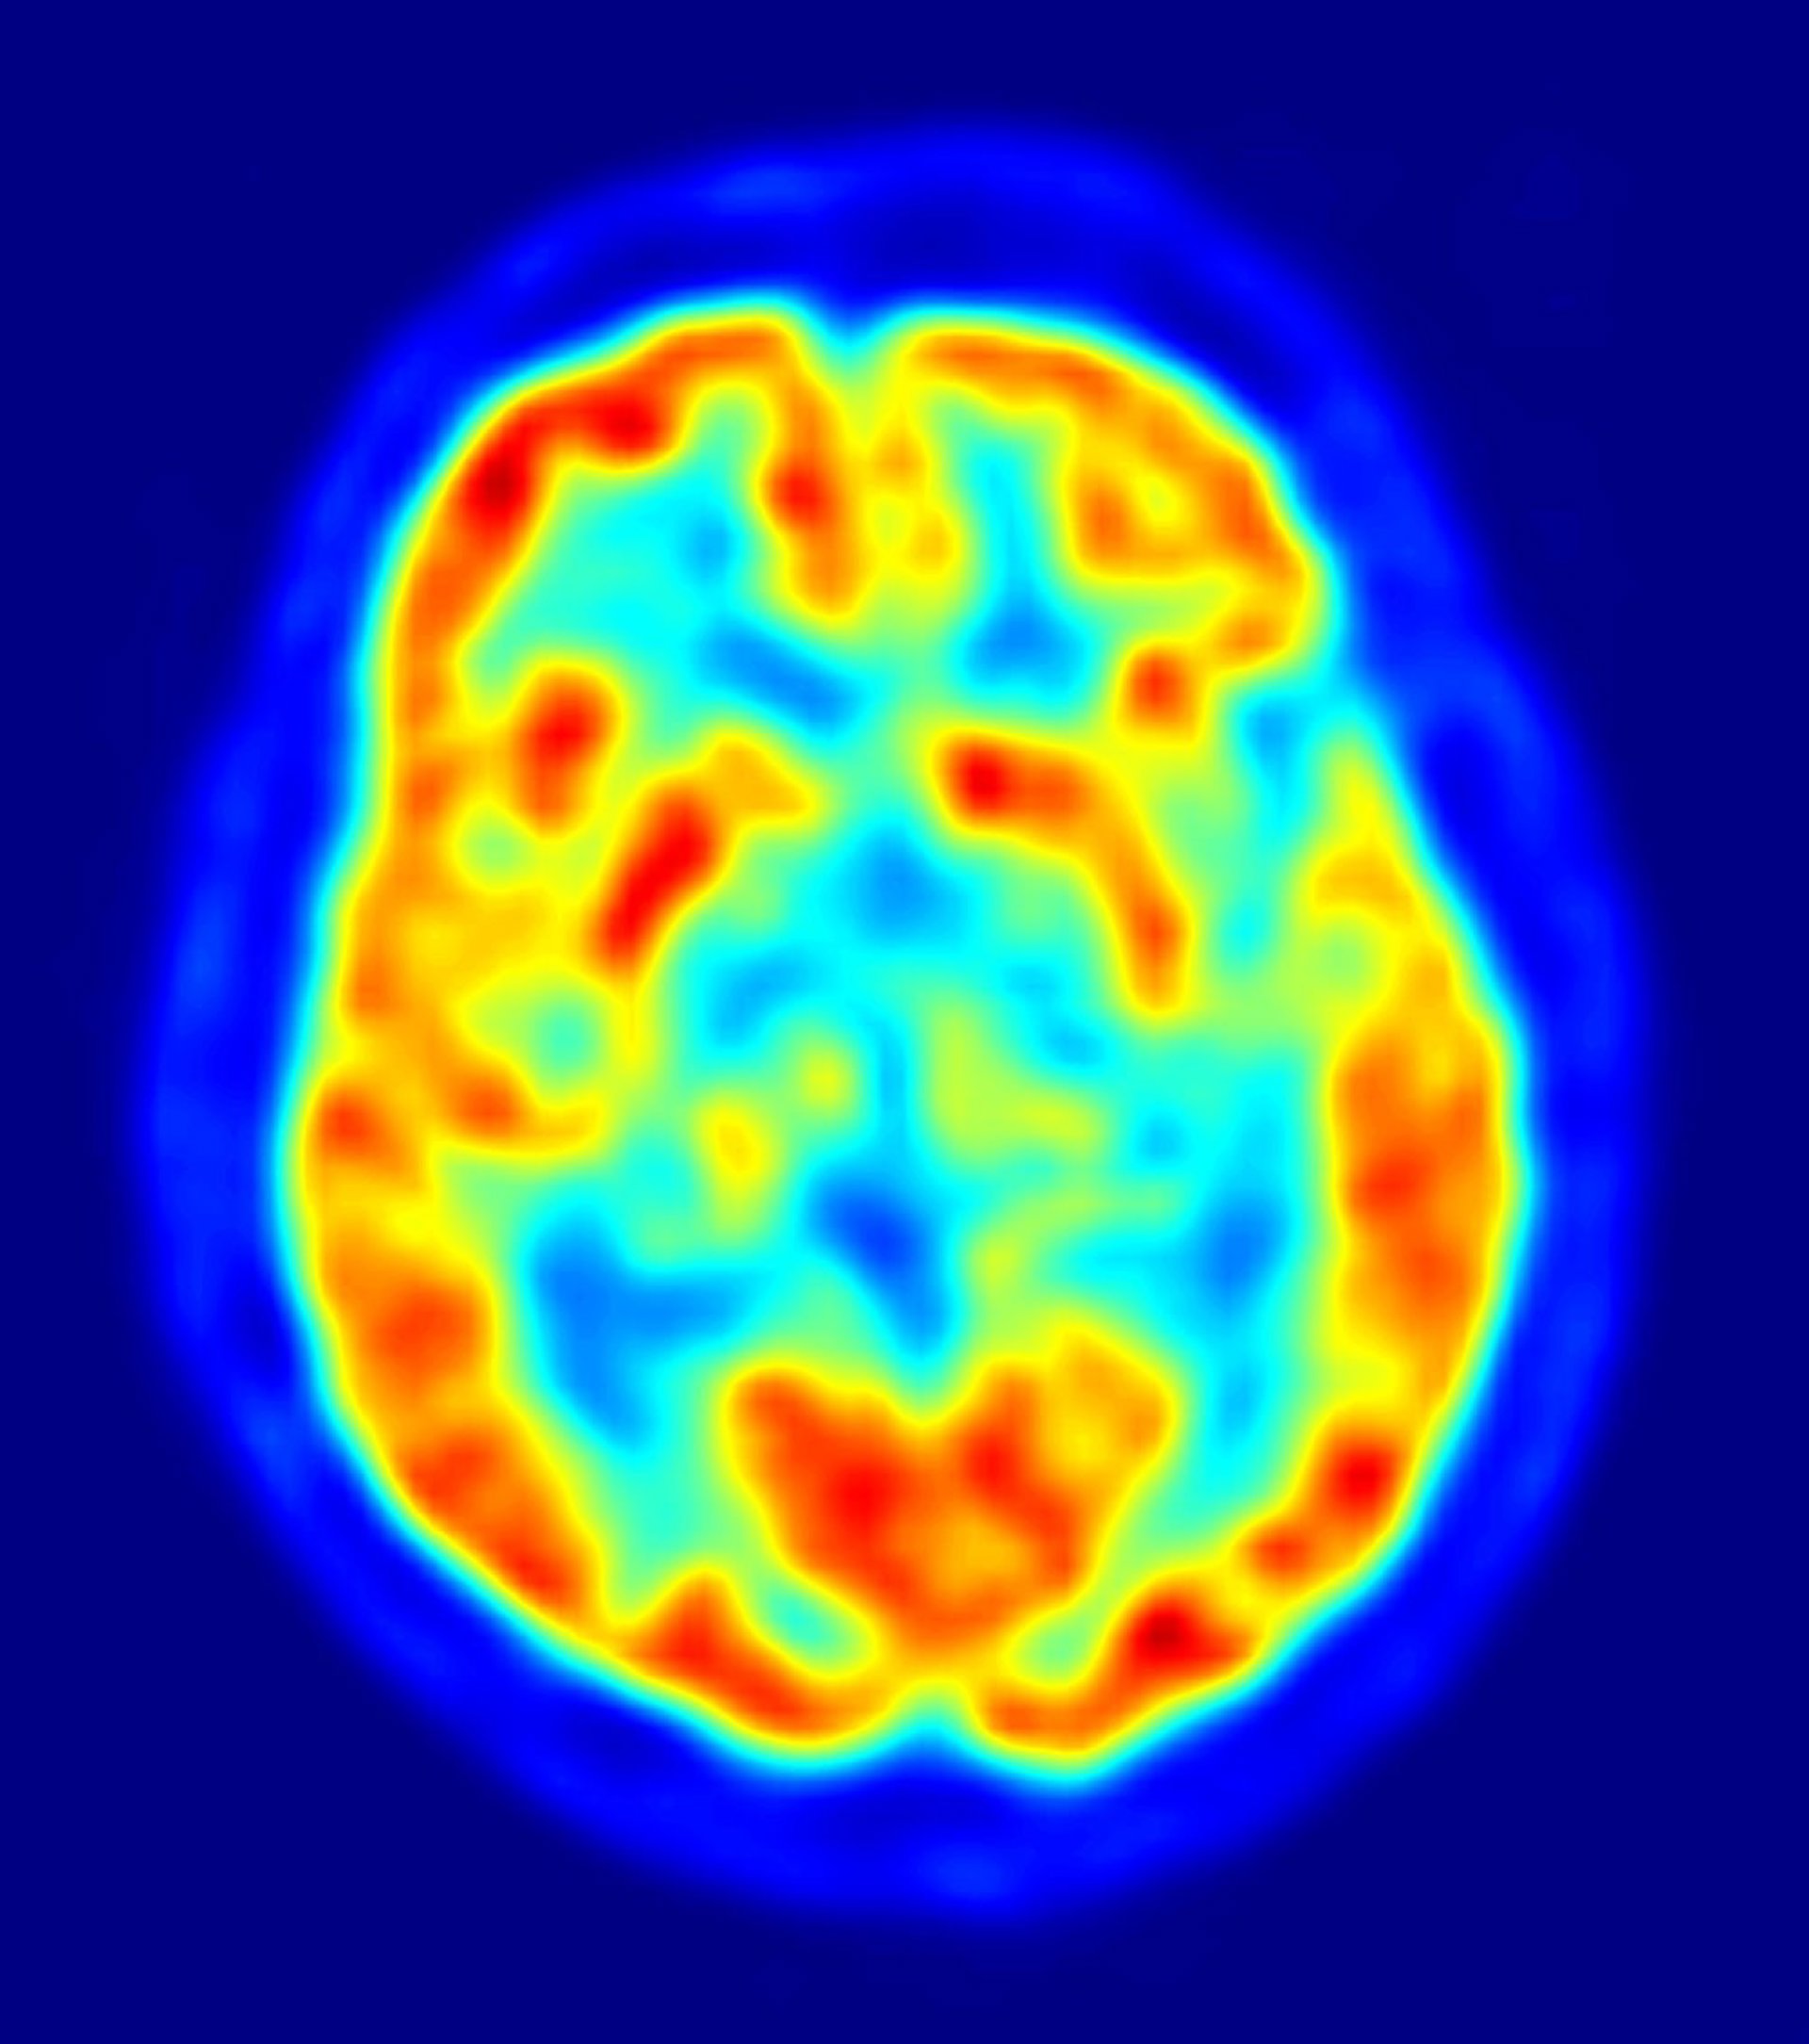

El cerebro humano contiene billones de conexiones neuronales, llamadas sinapsis, cuyo patrón de actividad controla todas las funciones cognitivas. Estas conexiones sinápticas son dinámicas, y están en constante cambio -este proceso, conocido como plasticidad sináptica, ha sido propuesto como la base celular para el aprendizaje y la memoria. De hecho, las alteraciones en los mecanismos de plasticidad sináptica son responsables de múltiples déficits cognitivos, como el autismo, la enfermedad de Alzheimer y varias formas de retraso mental.

Este péptido (llamado FGL) inicia una cascada de eventos dentro de la neurona que se traduce en la facilitación de la plasticidad sináptica. En concreto, los autores encontraron que el FGL provoca la inserción de nuevos receptores de neurotransmisores en las sinapsis, en una región del cerebro llamada hipocampo, conocida por estar involucrada en múltiples formas de aprendizaje, y en la memoria. Es importante destacar que, cuando este péptido se administró a un grupo de ratas, su capacidad para aprender y retener información espacial mejoró.